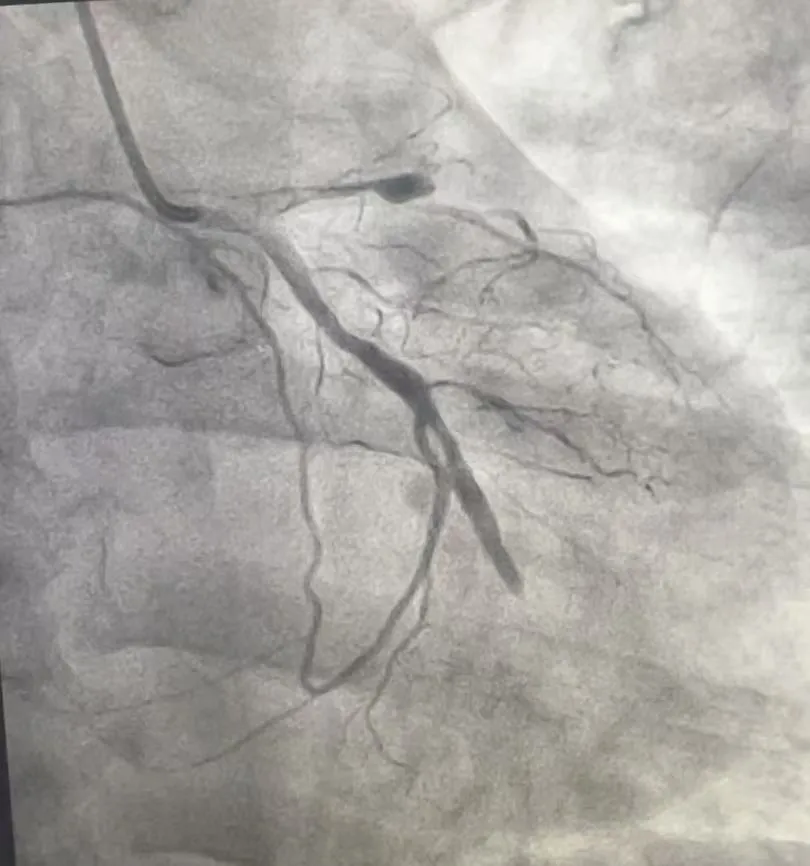

经过2小时的紧张奋战,前降支和回旋支成功开通,闭塞的血管重新“通车”,濒死的心肌迎来“救命血”。术中造影显示,支架贴壁良好,血流恢复至正常(TIMI3级),手术圆满成功。

(术后影像)